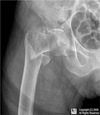

Intracapsular NOF

Subcapital fracture (intracapsular)

Intracapsular (Garden classification)

130

Intracapsular NOF fracture Garden classification type I

131

Intracapsular NOF fracture Garden classification type II

132

Intracapsular NOF fracture Garden classification type III

133

Intracapsular NOF fracture Garden classification type IV